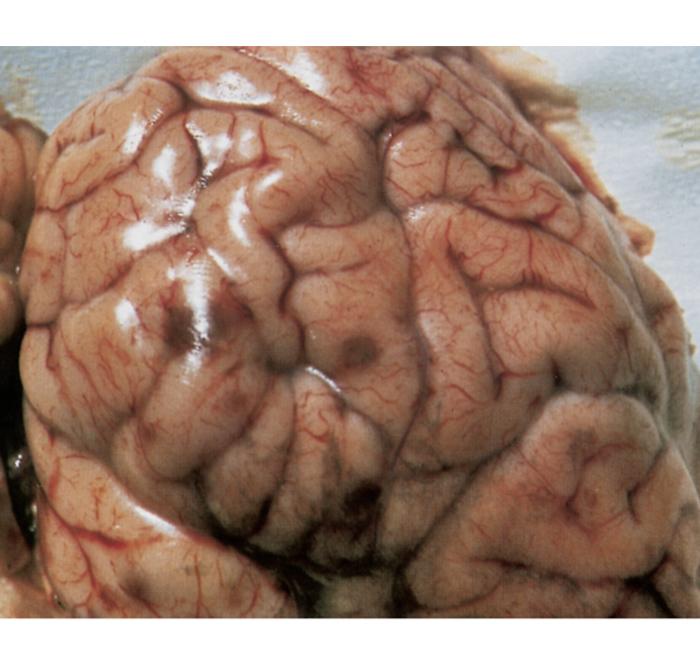

Macroscopically, in animals that have died from TME, the characteristic lesions are multiple infarcts in the central nervous system, which present as reddish-brown foci of haemorrhagic necrosis, varying in diameter from pinpoint to 40 mm (Figure 7).92, 126, 149 The extent and distribution of these infarcts in the brain and spinal cord are variable, but they occur in both the grey and white matter.

Lesions may be more prevalent in the thalamus, subthalamic nuclei and cerebrum, frequently near the junction of the grey and white matter.126 In some animals, most of the foci are very small (sometimes microscopic) and occur mainly in the spinal cord, while in others only a few very large lesions are present.